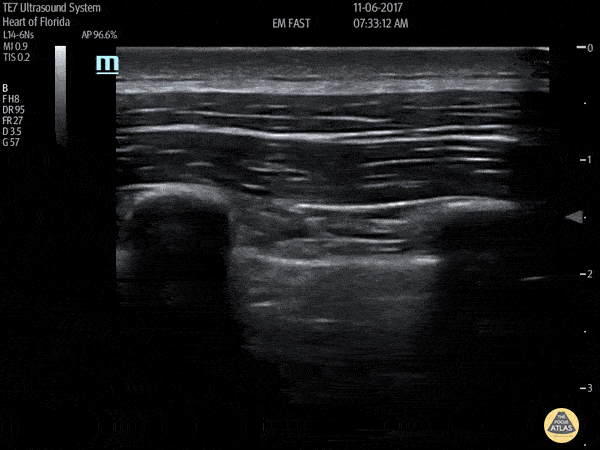

What vessel is the DVT in:

CFV